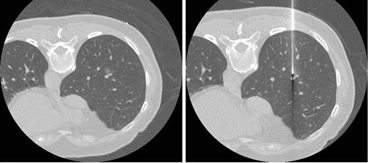

治療層面而言,透過低劑量電腦斷層找到的早期肺癌,多數能以手術治療或治癒,由於早期肺癌手術透過"電腦斷層導引之肺臟細針定位術" (圖1) 所切除的肺部組織相對較少,對於患者術後的肺功能與生活品質的影響很小。即使患者不適合手術或不願意接受手術,也可以選擇用"冷凍消融術治療" (圖2),對於初期肺癌也可以達到很好的腫瘤控制。

(圖一) 肺臟細針定位術是利用電腦斷層的定位與導引,透過細針經皮穿刺把定位線埋入病灶周邊,或者把染料注入病灶周邊,以利手術中辦識病灶,進行外科切除及病理檢查。 |